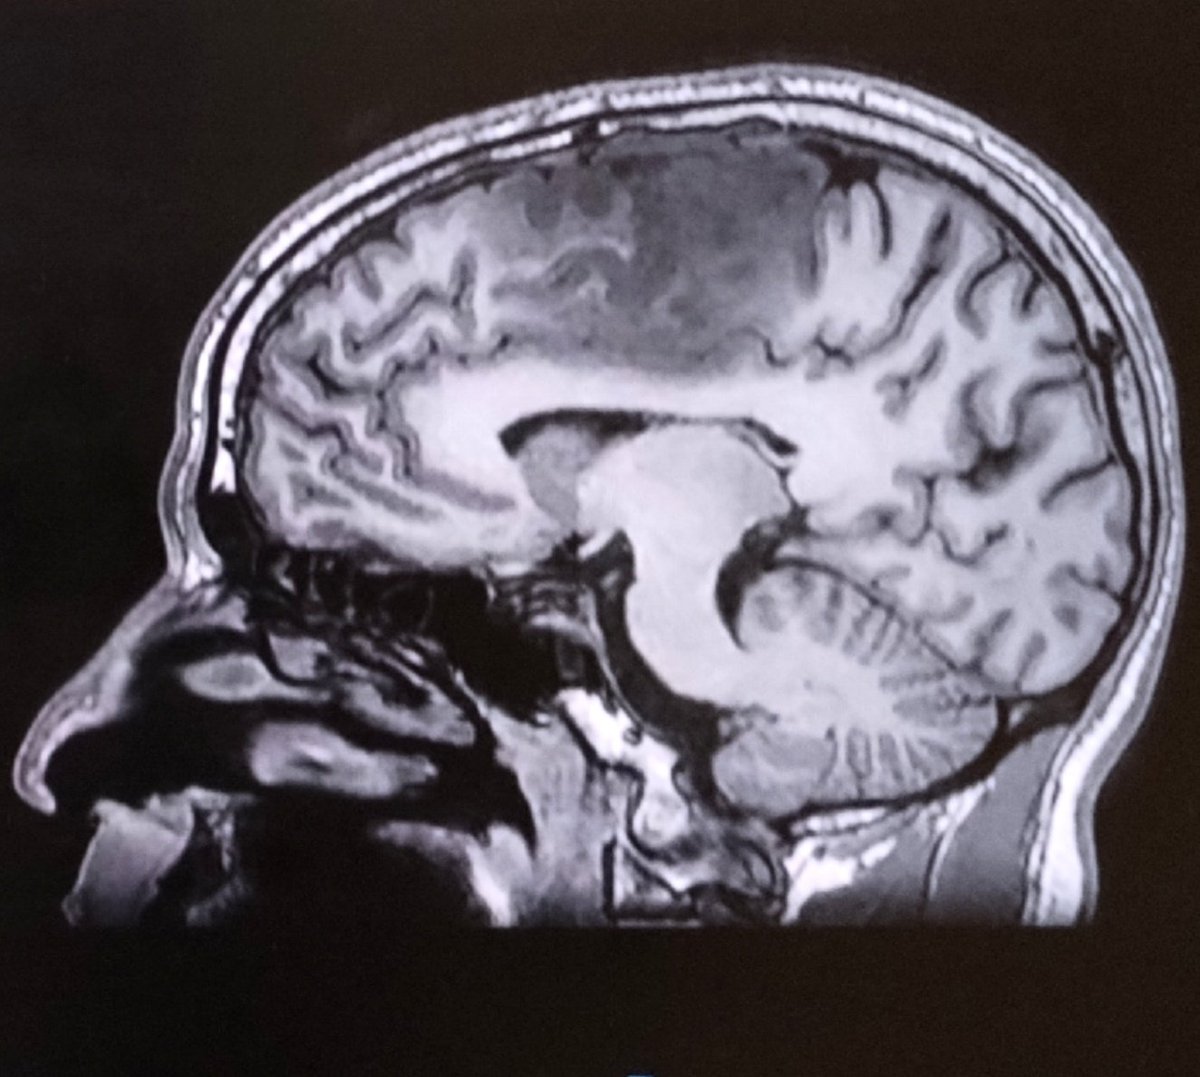

A 25 year old man comes to the emergency room with an acute history of hallucinations, persecutory delusions, aggresive behavior, psychomotor agitation. The mental status examination shows severe cognitive dysfunction. This is the brain image. Thoughts?